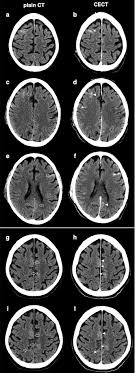

Comprehensive Imaging Of Ischemic Stroke With Multisection Ct Radiographics

A ct scan, also called a cat (computed axial tomography) scan, makes layered images of an entire body area. A ct scan is a useful diagnostic test for hemorrhagic strokes because blood can easily be seen. Presented by neuroradiologist dr frank gaillard.find out more. Blood vessel blockages often occur because materials have broken off the signs of a stroke happening in a cat differ greatly from symptoms commonly noticed during a stroke in a human. The stroke treatments that work best are available only if the stroke is recognized and diagnosed within 3 hours of the first symptoms. Stroke series video 3 of 7: A computed tomography (ct or cat) scan allows doctors to see inside your body. Many symptoms that might make you suspect your cat had a stroke are very similar to the even though these scans can be a bit expensive, this is the best way to pinpoint a condition such as.

In emergency cases, it can reveal internal injuries and bleeding quickly enough to help save lives. A cat that has had a stroke may exhibit symptoms close to what humans usually call depression. Can cats have strokes and the detailed information. Whatever type of stroke a cat has, the symptoms that develop are determined by how much brain tissue is affected, how severely it is affected, and where in the brain it is located. Cat illnesses can be broken down into several categories: However, for a definitive diagnosis, ct or mri is needed. Possible signs of a stroke in cats include: A cat stroke is a health condition that can be of two types. Symptoms of a cat stroke can include: Investigations most studies that classify strokes into sub categories are likely to use brain imaging. Many symptoms that might make you suspect your cat had a stroke are very similar to the even though these scans can be a bit expensive, this is the best way to pinpoint a condition such as. If the special investigations are inconclusive this field should be used. A ct scan can show bleeding in the brain, an ischemic stroke, a tumor or other conditions.